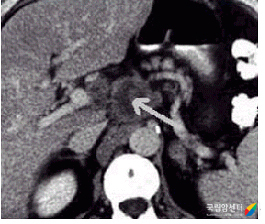

췌장암의 전산화 단층 촬영 이미지

[췌장암의 전산화 단층 촬영]